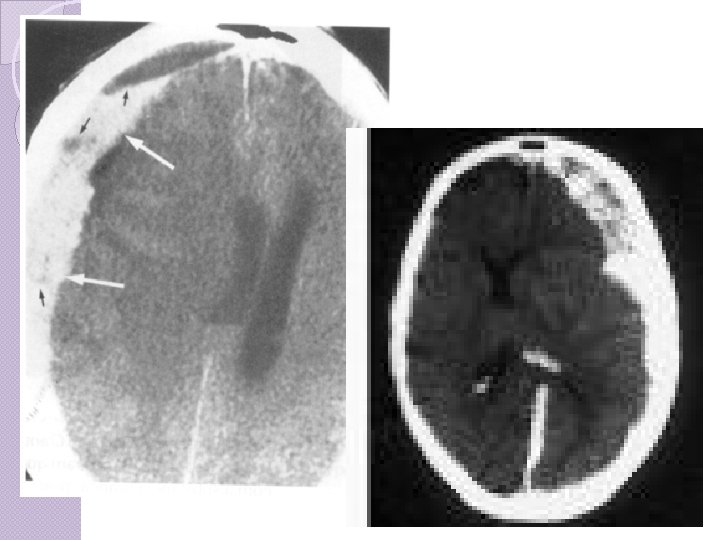

CLASSIFICAÇÃO Hematomas epidurais ◦ Osso e dura-máter ◦ Lente biconvexa, temporal ou têmporo-parietal, ◦ Ruptura da artéria meníngea média, causada por uma fratura. ◦ Tto precoce melhor prognóstico. ◦ Sintomático, > 1 cm, fossa posterior ◦ Clínica: intervalo lúcido seguido de “fala e morre”.

Hematomas Epidurais Ou extradurais ocorrem mais comumente por fratura da porção escamosa do osso temporal, em cuja face interna corre (em um sulco) a artéria meníngea média. Uma lesão desta causa um hematoma entre o osso e a dura-máter, de formação rápida, porque a pressão no vaso é arterial. Como a dura é aderida ao osso, os hematomas epidurais são circunscritos e arredondados. Forçam o lobo temporal em direção medial e provocam hérnia de uncus.

CLASSIFICAÇÃO Hematoma ◦ ◦ ◦ ◦ subdural: Mais freqüente que hematoma epidural Veia entre o córtex cerebral e o seio venoso. Recobrem toda a superfície do hemisfério. Comprometimento cerebral mais grave Prognóstico mais reservado que epidural Tto precoce, se sintomático Atraso maior que 4 hs: Mortalidade 59 69%;

Hematoma subdural A velocidade de formação do hematoma é variável de horas a dias. Inicialmente o sangue se coagula, mas vai lentamente se fluidificando por ação de fibrinolisinas. Os hematomas subdurais agudos podem causar hipertensão intracraniana elevada e hérnias. Além do tipo agudo, os hematomas subdurais podem ser crônicos, isto é, desenvolver-se lentamente, ao longo de semanas, após traumas pequenos esquecidos pelo paciente e desconhecidos familiares. São comuns em idosos e podem ser bilaterais

Hematoma subdural O quadro clínico é de deterioração gradual das funções mentais e da consciência, chegando ao coma, devido à compressão cerebral. Hematomas subdurais também podem ocorrer na infância por trauma obstétrico ou quedas.

FISIOPATOLOGIA DOS TCE * Hematomas Subdurais Agudos

Hematoma subdural